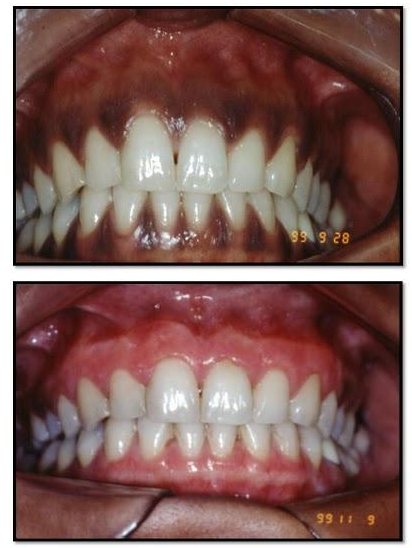

Caso clínico inicial

Após 15 dias da última cirúrgia

Gengivite Estabelecida Intensa (acima) e Caso Após Raspagem e Gengivectomia (abaixo)